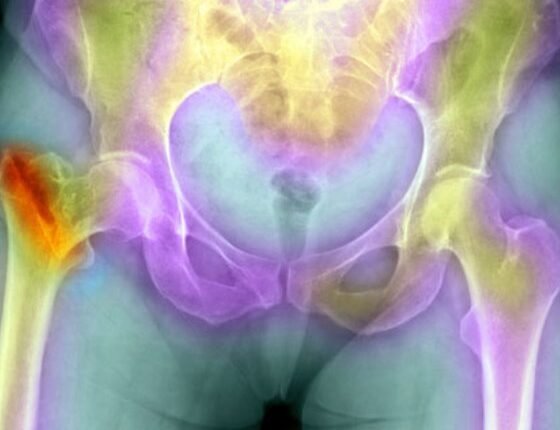

Ορισμένα κατάγματα συμβαίνουν, ύστερα από μια μεγάλη πτώση, ενώ άλλα μπορούν να συμβούν από κάτι φαινομενικά ακίνδυνο, όπως μια αγκαλιά ή ένα σκύψιμο. Τα κατάγματα λόγω οστεοπόρωσης είναι πιο συχνά στη σπονδυλική στήλη και στο ισχίο.

Μερικοί γιατροί χρησιμοποιούν τον τύπο FRAX (Εργαλείο Αξιολόγησης Κινδύνου Κατάγματος) για να εκτιμηθεί η πιθανότητά σας να σπάσετε ένα κόκαλο μέσα στα επόμενα 10 χρόνια. Η εξέταση συνυπολογίζει παρελθόντα κατάγματα, το φύλο, το κάπνισμα, τη χρήση αλκοόλ και μερικές φορές τα αποτελέσματα των εξετάσεων της οστικής πυκνότητας στο ισχίο, καθώς και άλλους παράγοντες.